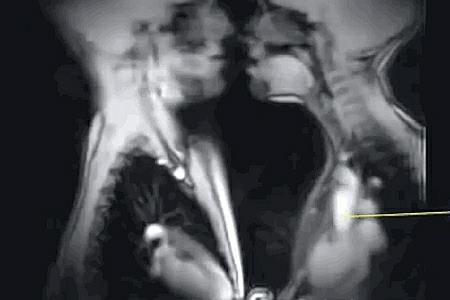

Mapiranjem molekula vode u tkivu ova mašina pravi impresivne snimke koji prate način na koji čovek govori, otkucaje ljudskog srca u uzbuđenom stanju, ali i vođenje ljubavi. A seks zapravo izgleda ovako:

Zatim možemo da vidimo krupan kadar stvarne scene seksa.